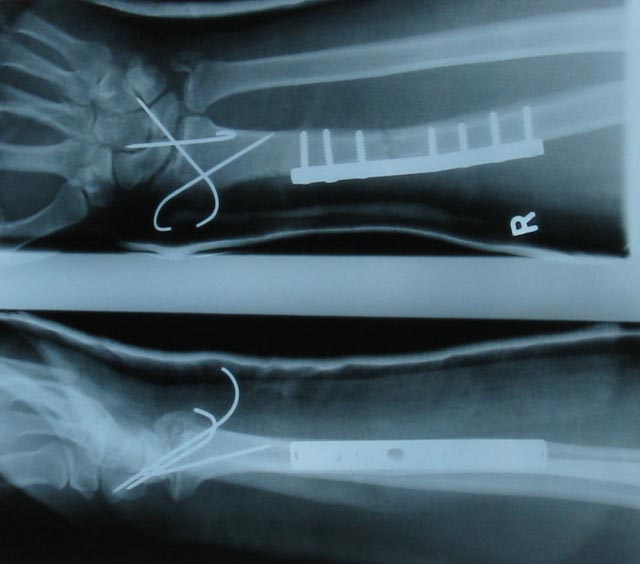

Fixed |

Many thanks to the orthopoedic surgeons at East Surrey Hospital. |